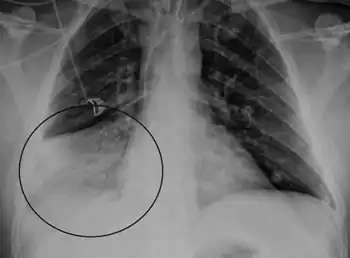

.png)

Human metapneumovirus (HMPV) was first classified as a pneumovirus in 2001. It is a negative-strand RNA virus that is the second most common cause of lower respiratory infection in young children. Pneumoviruses are intermediate in size between viruses of the families Paramyxoviridae and Orthomyxoviridae. Cytoplasmic inclusions are considerably more dense than those of other viruses in the family. Human metapneumovirus infection is very similar to the common cold; it is an upper respiratory infection. It will typically occur in the winter and early spring. This specific infection is most common in children, especially under the age of five. Common symptoms include runny nose, congestion, sore throat, cough, headache, and fever, which can be seen as a cold. It will typically go away after a few days. If this is seen in people over 75, then there is a cause for concern as it can turn to pneumonia.[19][20][21][22][23]